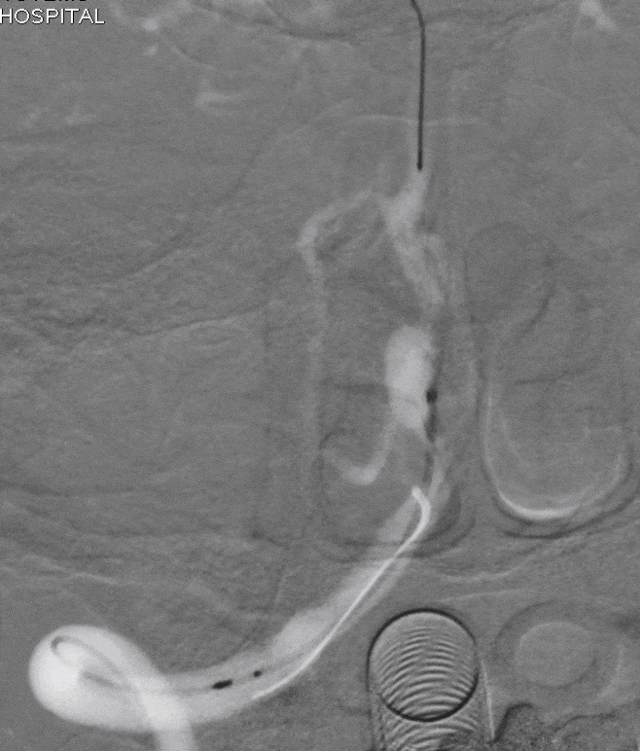

逐步释放Pipeline(3.00*30)。

支架完全释放,微导丝“按摩”支架。

术后即刻DSA。

术后即刻稀释造影:“拉直”可见支架贴壁良好。